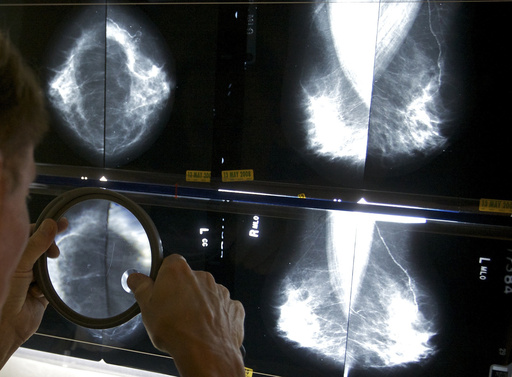

Regular mammograms to screen for breast cancer should start younger, at age 40, according to an influential U.S. task force. Women ages 40 to 74 should get screened every other year, the group said.

Previously, the task force had said women could choose to start breast cancer screening as young as 40, with a stronger recommendation that they get the exams every two years from age 50 through 74.

The announcement Tuesday from the U.S. Preventive Services Task Force makes official a draft recommendation announced last year. The recommendations were published in the Journal of the American Medical Association.